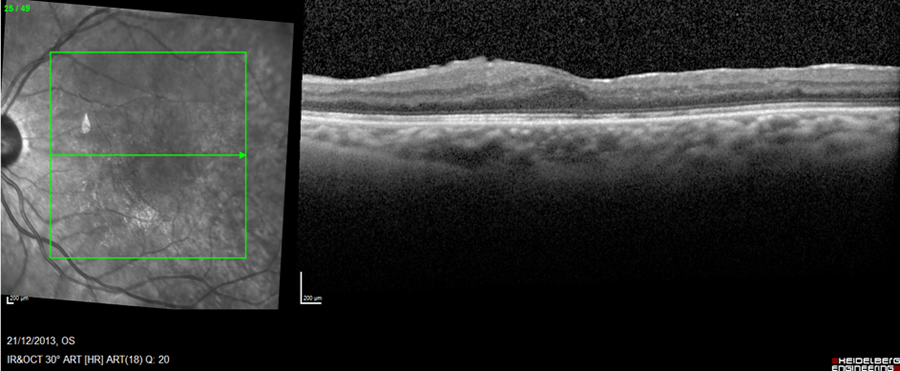

Figure 2: Post-operative appearance of diabetic retinal edema due to macular traction in optical coherence tomography imaging (post-diabetic retinopathy surgery)